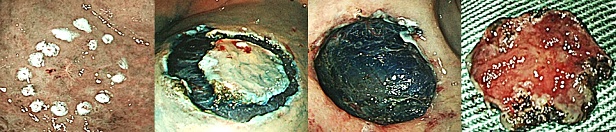

胃における早期がんに対する内視鏡治療手技が発達し、根治ができる症例が増加しており、従来の治療に代わる新しい治療法として注目されていますが、当院においても可能なかぎり早期がんに対しては 内視鏡的粘膜下層剥離術(Endoscopic submucosal dissection、ESD)を行っております。治療手技は内視鏡治療用の電気のメスで直接、病変部を切って剥ぎ取る方法です。